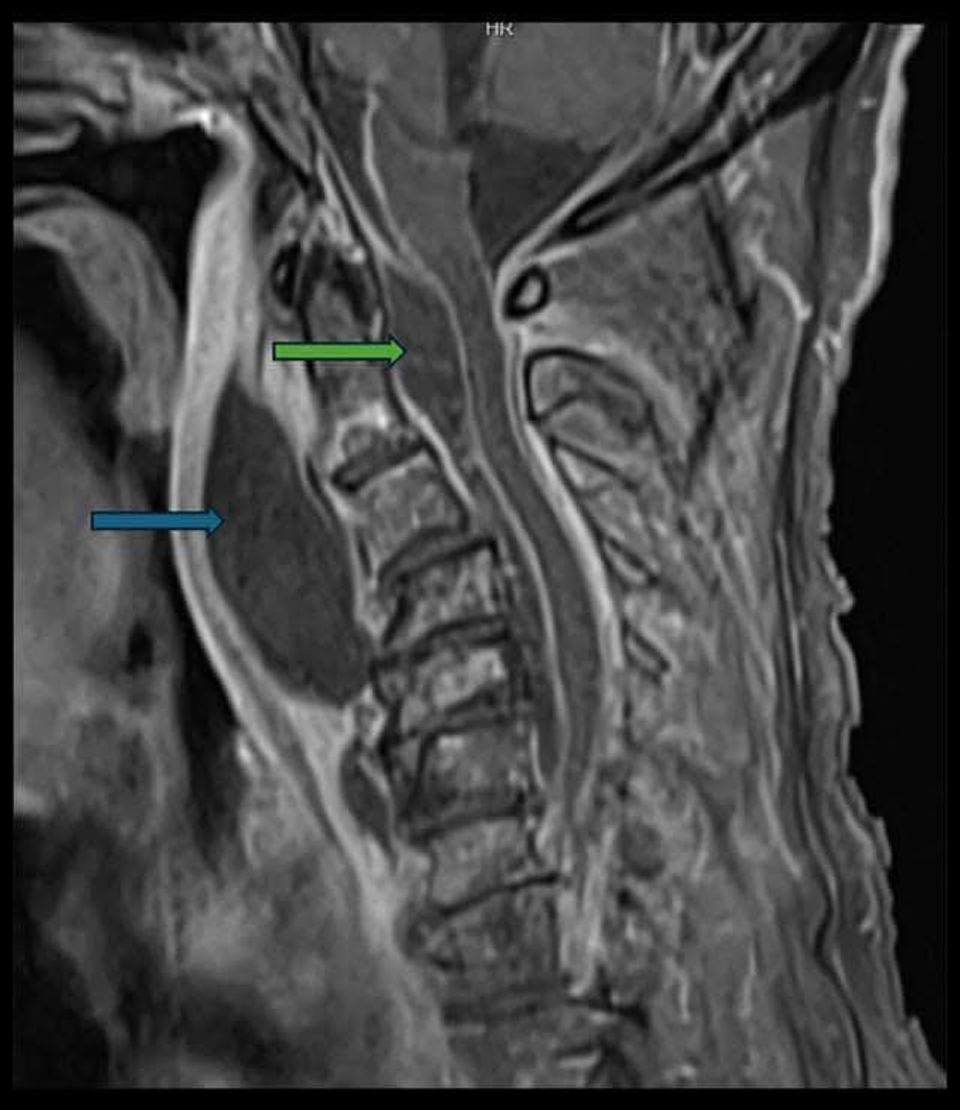

“ที่ห้องฉุกเฉิน แพทย์เห็นว่า ลิ้นไก่ของผู้ป่วยถูกดันไปด้านหน้า คอด้านหลังบวมเหมือนมีอะไรมาดัน และผู้ป่วยเริ่มมีเสียงหายใจคล้ายเสียงกรน (stridor) แต่ไม่ได้หลับ เคสนี้ทำ CT และ MRI มีฝีหนองก้อนใหญ่ อยู่ในช่องหลังคอ (retropharyngeal space) กดผนังคอเข้าด้านหน้า จนช่องลมที่ควรโล่ง เหลือแค่นิดเดียว อีกไม่กี่ชั่วโมง อาจปิดทางเดินหายใจได้เลย

จุดเริ่มต้นทั้งหมดมาจาก ฟันผุที่ลุกลาม ทำให้ติดเชื้อไปที่กระดูกขากรรไกร ต่อมน้ำเหลือง โดยช่องหลังคอ เป็นเส้นทางการลุกลามที่อันตรายแบบไม่รู้ตัว มารู้ตัวตอนเริ่มไปคอแล้ว และยังพบว่ามีการลุกลามเข้าไปโพรงเยื่อหุ้มไขสันหลังแล้วด้วย (Epidural abscess)